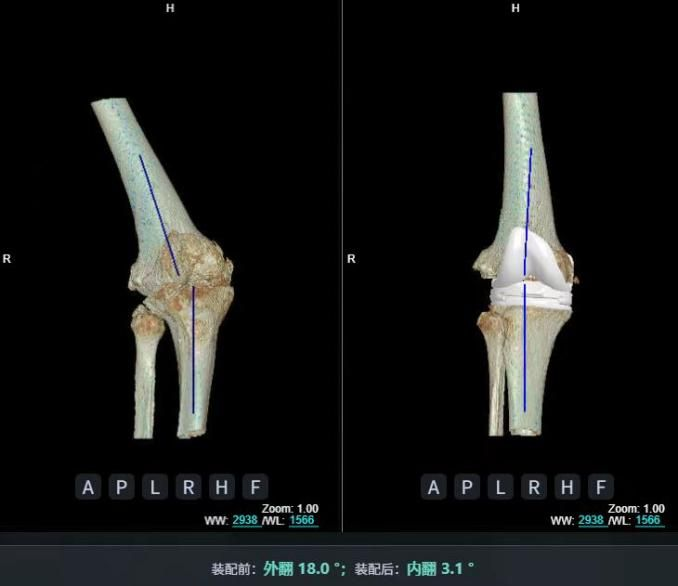

4.2 APTT-HTO脛骨高位截骨術(shù)

2025年7月,貴州醫(yī)科大學(xué)附屬醫(yī)院骨科團(tuán)隊(duì)原創(chuàng)研發(fā)的腘肌前結(jié)節(jié)中脛骨高位截骨保膝術(shù)(Anterior Popliteus Transtibial Tuberosity-High Tibial Osteotomy, APTT-HTO)及其提出的脛骨結(jié)節(jié)分區(qū)與腘肌保護(hù)理論,登上了國際頂尖學(xué)術(shù)舞臺。該成果在全球最具影響力的專業(yè)會議之一——日本骨科協(xié)會第98屆年會上進(jìn)行了兩次學(xué)術(shù)發(fā)言。[8]

該手術(shù)具有經(jīng)皮微創(chuàng)、保留原生膝關(guān)節(jié)結(jié)構(gòu)、符合階梯治療原則等優(yōu)勢,通過調(diào)整下肢力線可促進(jìn)部分軟骨再生,術(shù)后關(guān)節(jié)功能接近正常(如下蹲、爬山),患者還能從事中重體力勞動。相比其他術(shù)式,其有效規(guī)避了髕骨低位、血管損傷、合頁骨折等潛在并發(fā)癥。

目前,APTT-HTO技術(shù)已成功應(yīng)用于千余名患者,幫助保留自身膝關(guān)節(jié)。此類保膝手術(shù)適用于單間室膝關(guān)節(jié)炎患者(如 “羅圈腿”),核心是通過調(diào)整力線糾正畸形,減輕磨損間室壓力、發(fā)揮健康間室作用,延長膝關(guān)節(jié)壽命。若出現(xiàn)膝關(guān)節(jié)疼痛、保守治療無效且X線顯示關(guān)節(jié)間隙部分狹窄,建議及時(shí)就醫(yī)評估是否適合手術(shù)。